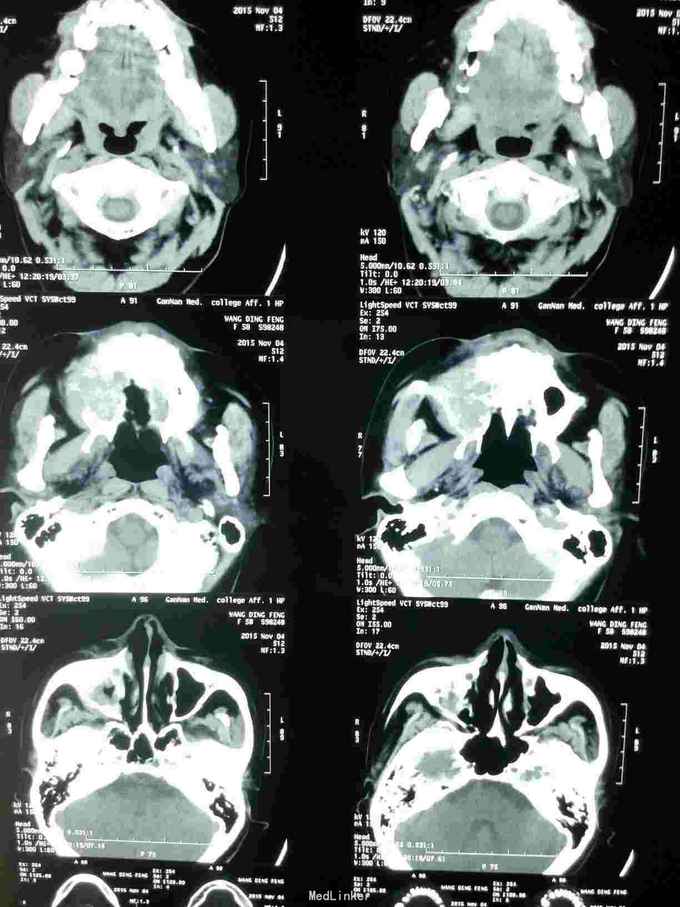

患者女,58岁,因“右上颌后区牙龈溃烂1月”入院 患者于2月前感右上颌后区麻木不适感,一月前在当地医院检查发现上颌后区牙龈溃烂,行抗炎治疗无好转。就诊于我院门诊后行病理检查提示:磷状细胞癌。

查体:心肺腹无明显异常。 专科:右上颌区颊颚侧龈、牙槽脊表面溃烂,凹凸不平,呈不规则溃疡,边缘欠佳。 辅查:CT+三围重建等,见图!

诊断:右上后牙区牙龈磷状细胞癌 治疗:右上后牙区牙龈磷状细胞癌病灶扩大切除+右上颌骨全切+右肩胛舌骨肌上淋巴结清扫术